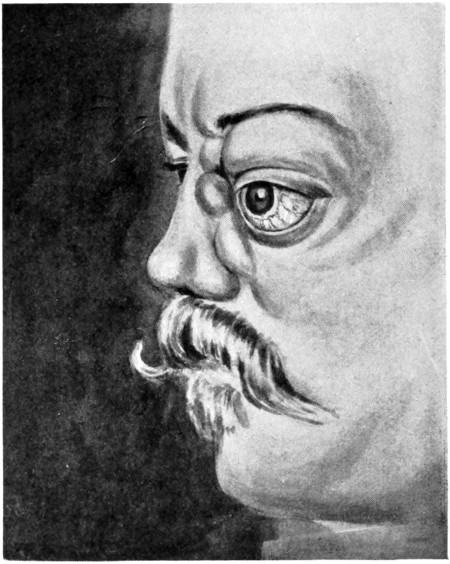

| 61. A case of traumatic orbital aneurysm | 207 |